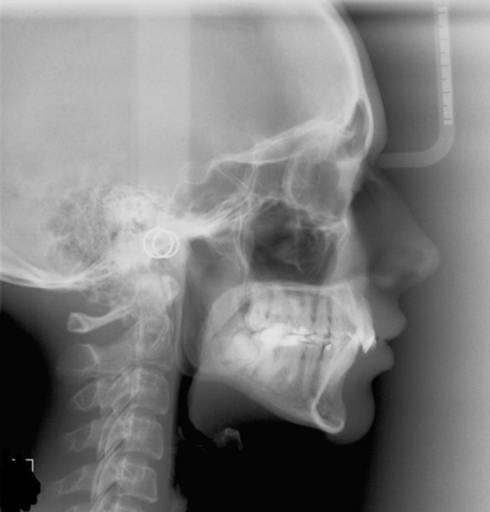

I have a bad underbite. When I was around 12 or 13 I had braces. At that time they asked if I would like to have surgery to fix my underbite and I said no because it never really bothered me. I'm almost 25 now and I'm starting to have pain in my jaw. Some days it feels as if I can't relax it and it feels really tight. I also get headaches a lot and the pain goes from my jaw all the way to my head. If I wanted to get surgery would I have to get braces again since I have already had them? Can you get headaches from your jaw being out of line?

Should I get jaw surgery?

Hello, I have an under bite, and while my braces were on, I was told to get jaw surgery. However, I rejected it at the time and so the orthodontists did their best to line up my teeth using braces. I now have my braces off, but I'm not completely...